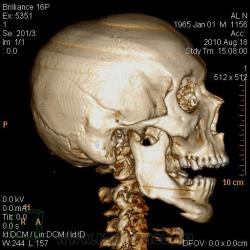

ЗЧМТ, правополушарная эпи-субдуральная гематома (четко не вижу), с дислокацией срединных структур мозга влево и аксиально, с компремированием боковых, преимущественно, правого бокового и третьего желудочков, САК, КТ-признаки набухания вещества головного мозга. Линейный перелом правой теменной и височной костей.

Я выставила линейный перелом правой теменной и височной кости с переходом на основание, эпи-субдуральная гематома 80 мл, САК, латеральная (13 мм) и аксиальная дислокация, отек вещества мозга, гемосинус основной пазухи. На операции оказалась эпидуральная гематома (но на мой взгляд, оценить ВСЮ гематому через трепанационное отверстие довольно сложно).

Здесь гематома больше лентовидная, распространяется по все поверхности полушария от основая до макушки, и от лба до затылка. Довольно характерная картина субдуральной гематомы.